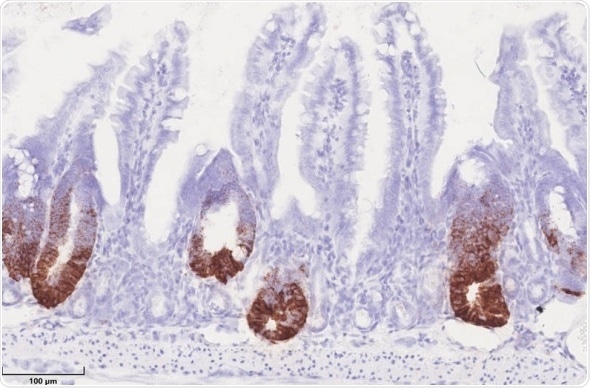

HSP60 in mitochondria control stem cell proliferation in the gut epithelium. HSP60 negative crypts show a loss of positive stem cells (brown staining), while stem cells hyperproliferation occurs in HSP60 positive gut epithelium. (Photo: Team Haller/ TUM)

On one hand, the respiratory capacity and the cellular ATP levels were reduced, both key tasks of the mitochondrion, the powerhouse of the cell. At the same time, Professor Haller and his team observed that all cells without HSP60 presented changes. Stem cells lost their ability to self-regenerate, while surrounding epithelial cells initiated a growth program.

"But the reaction to the lack of HSP60 was startling", says Haller — "because although stem cells lost their characteristic properties, the stressed cells in the surrounding intestinal mucus wall activated a growth program leading first to hyperproliferation that finally ended in tissue regeneration." The cells with disrupted mitochondrial functions send out growth factors as a "call for help". Using the stress response program, they ensure that the residing stem cells with intact mitochondria divide abundantly; these new, intact cells then replace the other stressed ones.